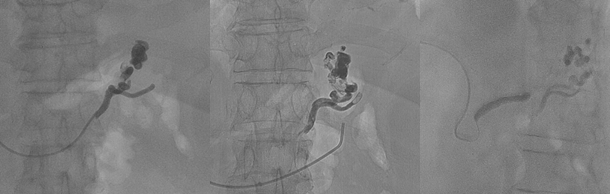

Dùng kim Angiocath chọc vào nhánh TM rốn dưới hướng dẫn siêu âm, sau đó dùng dụng cụ can thiệp dưới hướng dẫn của DSA đi vào TM cửa.

Hình 3: Tiếp cận TM cửa qua TM rốn

Dưới hướng dẫn cửa DSA tiếp cận các nhánh TM cấp máu cho búi giãn bao gồm TM vị trái, TM vị sau và TM vị ngắn, chụp chọn lọc từng nhánh, bơm vật liệu tắc mạch là keo sinh học, chụp đánh giá lại sau mỗi lần chụp để có thể nút tắc triệt để

Hình 4: Nút tắc các nhánh nuôi bằng keo